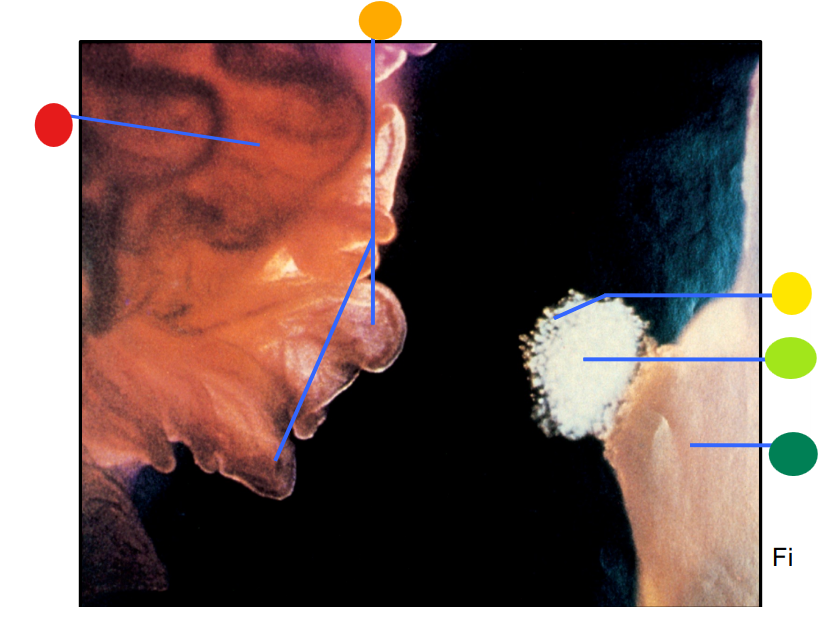

red

infundibulum

orange

fimbriae

yellow

cumulus oophorus

light green

oocyte

dark green

ovary

How is the egg and culmulus oophorus drawn into the infundibulum after the rupture of a mature follicle?

via ciliary action